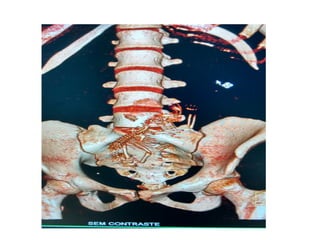

RECONSTRUÇÃO 3D

PLANEJAMENTOS DE RXT